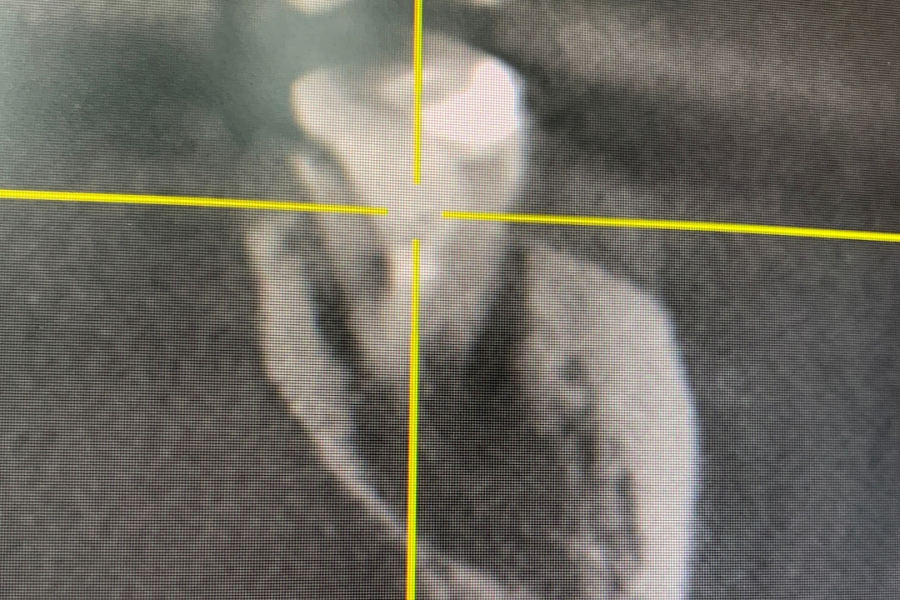

Принято решение удалить зуб и провести щадящий кюретаж с целью не повредить нижний челюстной нерв, т.к. это может привести к онемению губы и подбородка.